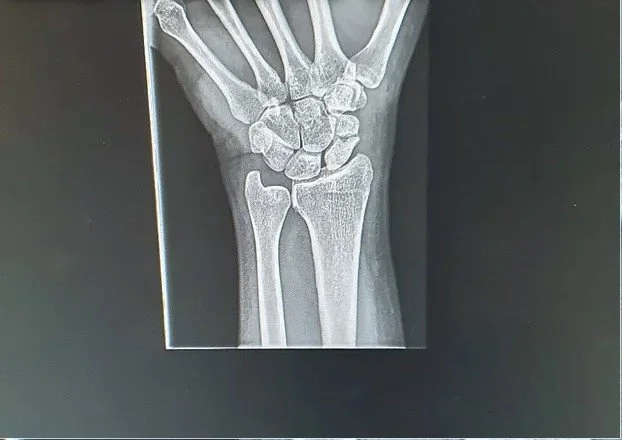

Radiology